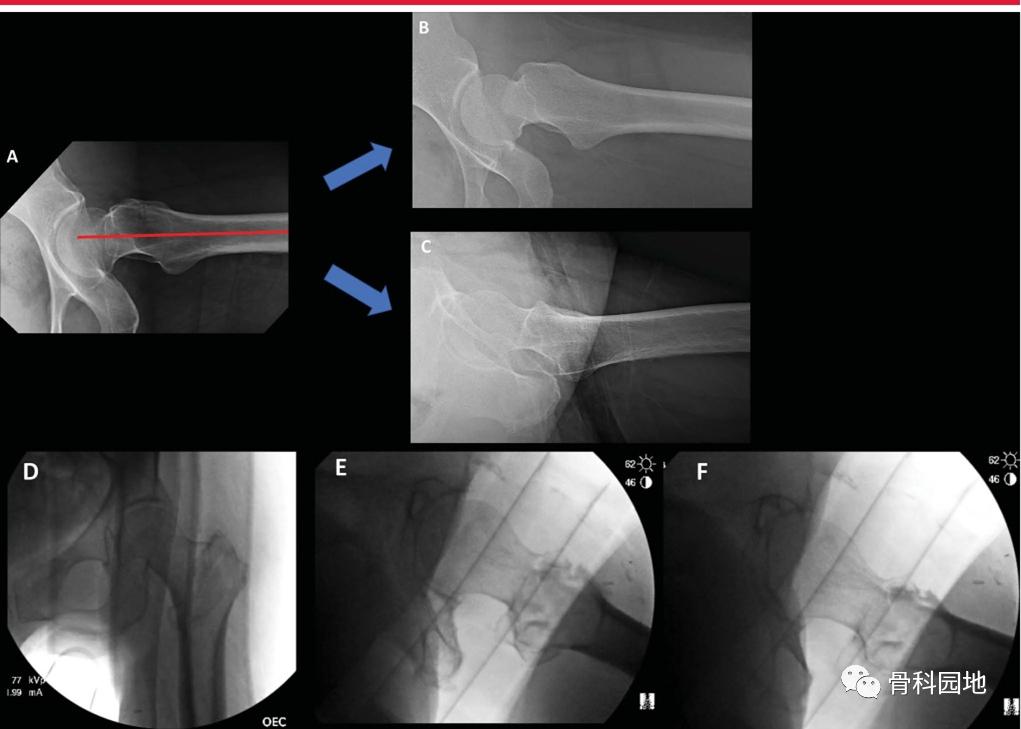

专门的髋部x线片是评估骨折形态的必要条件。虽然大转子尖端与股骨头中心之间的关系通常是共面的,但正位骨盆或对侧髋关节x线片可以帮助评估天然解剖结构和潜在的髋外翻(coxa valga )或者髋内翻(coxa vara) (下图A正常颈干角,B髋外翻,C髋内翻)

内旋牵引x线片在术前计划中特别有用。特别地,Khurana等人证实,内旋牵引x线片显著提高了股骨近端骨折分类的诊断准确性、可信度和观察者间的一致性。此外,术前牵引x线片可以帮助外科医生确定闭合复位动作何时可能成功(图2)。

逆转子间骨折在复位和植入方面存在特别的挑战。需区分高能和低能粗隆部骨折,因为这些骨折的“表现”不同(下图)。虽然低能骨折可以在骨折手术台上通过闭合复位成功治疗,但高能骨折通常需要经皮或开放复位技术。

左侧髋关节侧位透视图显示尽管骨折手术台上有足够的牵引和旋转,骨折碎片仍有较大的移位。

为了评估骨折固定期间的透视视图,必须了解完整股骨的近端股骨关系,以及它们如何随透视光束位置、腿部位置和正常解剖变异而变化。股骨近端图像显示股骨粗隆尖与股骨头中心的标准关系,当股骨近端向外旋转时,股骨颈轴角度增加,股骨颈似乎变短(下图)。

x线片显示同一髋从内旋(IR)到外旋(ER)的AP透视图像。注意髋关节从IR到ER的距骨轮廓的变化。当颈干角从屈曲/IR到屈曲/外旋时,注意颈干角角度的外观。

术中髋关节侧位透视对复位和植入物的评估。A,侧位图像最适合植入物,显示股骨头、股骨颈和股骨轴共线。B,同一髋关节内旋侧位片。C,同一髋的外旋转侧位图像,是评估前内侧皮质支撑和髋粗隆部骨折复位的最佳选择。D - F,术中透视图像获得骨折台上仰卧位,显示AP (D)、侧位植入物(E)和侧位复位(F)视图